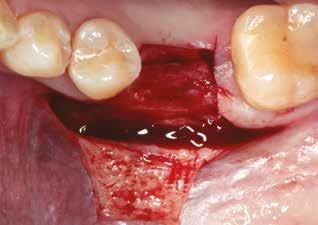

A foggyökér óvatos, atraumatikus eltávolítását követően excochleáltuk a parodontális és periapikális gyulladásos folyamatok eredményeként jelen lévő sarjszövetet. Az alapos tisztítás és a bukkális csontfal hiánya miatt indokolt membrántechnika megfelelő kivitelezése céljából mukoperioszteális lebenyt képeztünk, a lebeny tervezésénél arra törekedtünk, hogy az a lehető legkisebb méretű legyen és a második kisőrlő fog helyén lévő implantátum hámtapadását ne érintse, illetve, hogy lehetővé tegye a szemfog parodontális kezelését is (3., 4. ábra). Az alveoláris csont megőrzésének és regenerációjának segítése céljából a fog eltávolításával egy időben alveólus prezervációt végeztünk Stikcy Bone™ és PRF membránok segítségével, melyek előállításánál követtük a J. Choukroun által megadott vérvételi és centrifugálási protokollt (20). Kizárólag Process for PRF Duo Quattro System eszközöket, centrifugát, vérvételi egységet és csöveket, a membránok előállításához PRF Box-ot használtunk. Az A-PRF és S-PRF csöveket a PomPac eljárásnak megfelelően 4 °C-ra előhűtöttük. A Stikcy Bone™ készítmény előállításához Purgo™ xenografot használtunk. Az alveolust a grafttal feltöltöttük, tömörítő műszerrel enyhe kompreszsziót, illetve vertikális irányban 10 százaléknyi túlkompen-

zációt alkalmaztunk  (5., 6. ábra). Ezt követően a palatinális marginális gingivát óvatosan alápreparálva a bukkális defektust, valamint az okkluzális felszínt keresztirányban

A-PRF membránokkal borítottuk (7. ábra). A mukogingivális lebenyt – annak megnyújtása nélkül – a helyére fektettük és varratokkal rögzítettük, per primam sebzárást nem végeztünk (8., 9. ábra). A varratokat 2 hét után távolítottuk el, a varratszedésig a sebgyógyulás támogatására per os 1000 mg/nap C- és 12 000 NE/nap D-vitamint adtunk (20). A műtéti beavatkozást 24 hét gyógyulási időszak követte, melynek során sem helyi, sem gyógyszeres kezelés nem történt, az esztétikum javítása érdekében a páciens ideiglenes kivehető fogpótlást használt. A csontos gyógyulás ellenőrzése és az implantáció tervezése céljából állcsonti CT felvételt készítettünk, illetve lenyomatvételt végeztünk. A CT felvételen tökéletes csontos gyógyulást észleltünk, az alveolaris csont volumene teljes mértékben megtartott volt (10. ábra), a klinikai kép is ennek megfelelően alakult (11., 12. ábra)